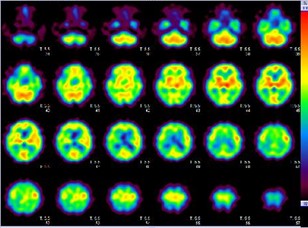

123I ]β-CIT シンチグラム (通称 DATシンチ)

PD 線条体(特に後部)の取り込み(C I T値)低下

正常 線条体の取り込みは保たれている